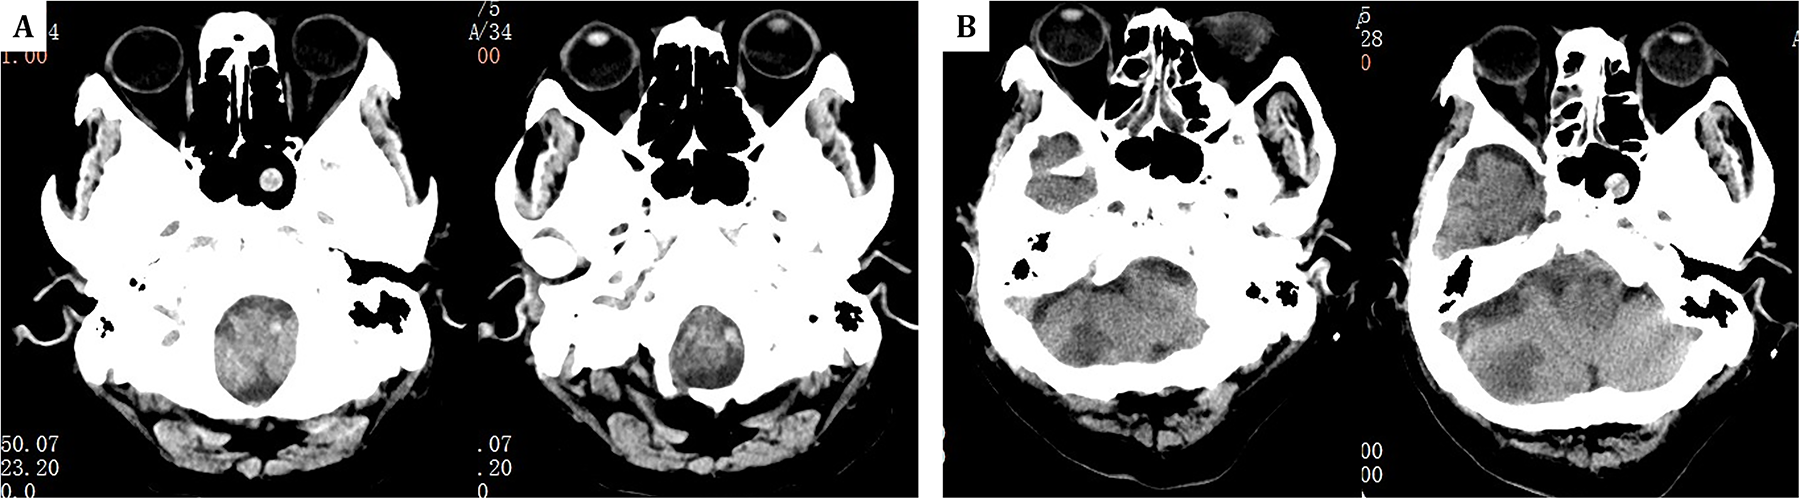

In this case, mNGS quickly identified the pathogen and helped diagnose Aspergillus meningoencephalitis, suggesting a possible nasal sinus origin, as bronchoalveolar lavage did not detect Aspergillus fumigatus and newly developed sinusitis was noted on cranial CT (Figure 4). Common complications of Aspergillus endocarditis include cardiac issues, arterial embolism, mycotic aneurysms, metastatic abscesses, and neurological complications (22, 23). Embolization occurs in 54% of cases, most frequently affecting the brain, but also the spleen, kidneys, and lungs (1, 4). This patient experienced cerebral embolism and meningoencephalitis, with early recurrent focal neurological symptoms and imaging showing multiple cerebral emboli.

Figure 4

(A) One year prior, head CT revealed only a sphenoid sinus cyst. (B) The current admission's follow-up head CT at the same level now shows the sphenoid sinus cyst along with additional findings of right-sided ethmoid sinusitis.